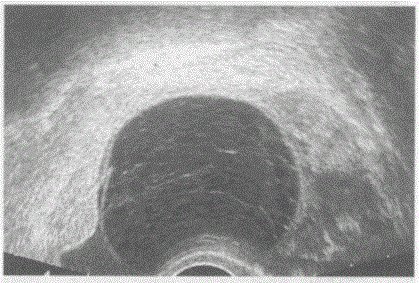

临床资料:女,27岁,常规体检。超声综合描述:经阴道扫查左卵巢可见4.2cm×3.1cm无回声区,边界清晰,形态规则,内呈网状分隔,包膜完整。...

问题 临床资料:女,27岁,常规体检。 超声综合描述:经阴道扫查左卵巢可见4.2cm×3.1cm无回声区,边界清晰,形态规则,内呈网状分隔,包膜完整。 超声提示:

选项 A.左卵巢黄素囊肿 B.左卵巢畸胎瘤 C.左卵巢黄体囊肿 D.左卵巢巧克力囊肿

答案 C